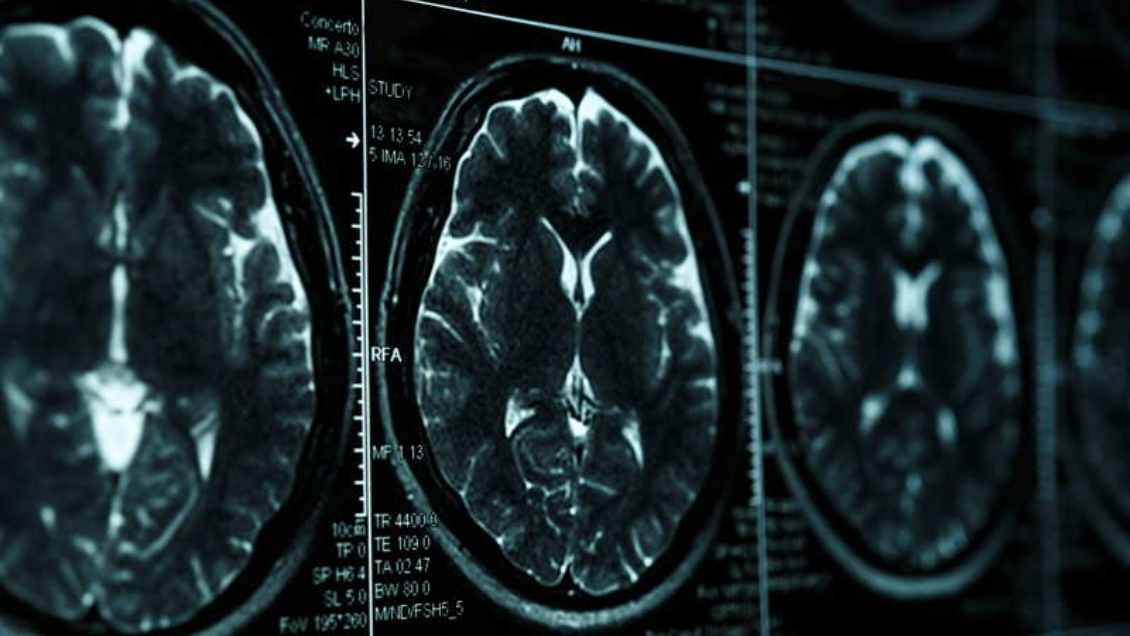

Un nuevo ensayo clínico ha confirmado la eficacia del fármaco experimental lecanemab para ralentizar los efectos de la enfermedad de Alzheimer, aunque también ha señalado sus efectos adversos y la necesidad de estudios más prolongados.

El estudio de fase tres, publicado por The New England Journal of Medicine, fue llevado a cabo en diversos centros médicos durante 18 meses, con un total de 1.795 pacientes de entre 50 y 90 años y en las primeras etapas de la enfermedad.

Los resultados del ensayo clínico muestran que el anticuerpo monoclonal "reduce los marcadores de amiloiodes en el alzhéimer temprano, y resulta en un declive moderadamente inferior en las mediciones cognitivas y de funciones en comparación con el placebo".

En particular, el fármaco permitió ralentizar este declive en aproximadamente un cuarto durante los 18 meses que duró el estudio.

Las conclusiones del estudio añaden no obstante que el fármaco "fue asociado con efectos adversos" y subraya la necesidad de "ensayos más prolongados para determinar la eficacia y la seguridad del lecanemab en el alzhéimer temprano".